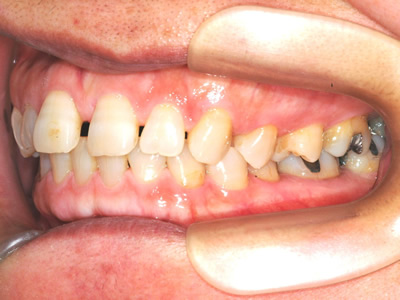

上顎前歯のガタガタと前歯の反対咬合を気にして来院されました。上下顎の左右第一小臼歯 (4番目の歯) を抜歯し、マルチブラケット装置で治療しました。治療期間は2年10ヶ月かかりました。

初診時